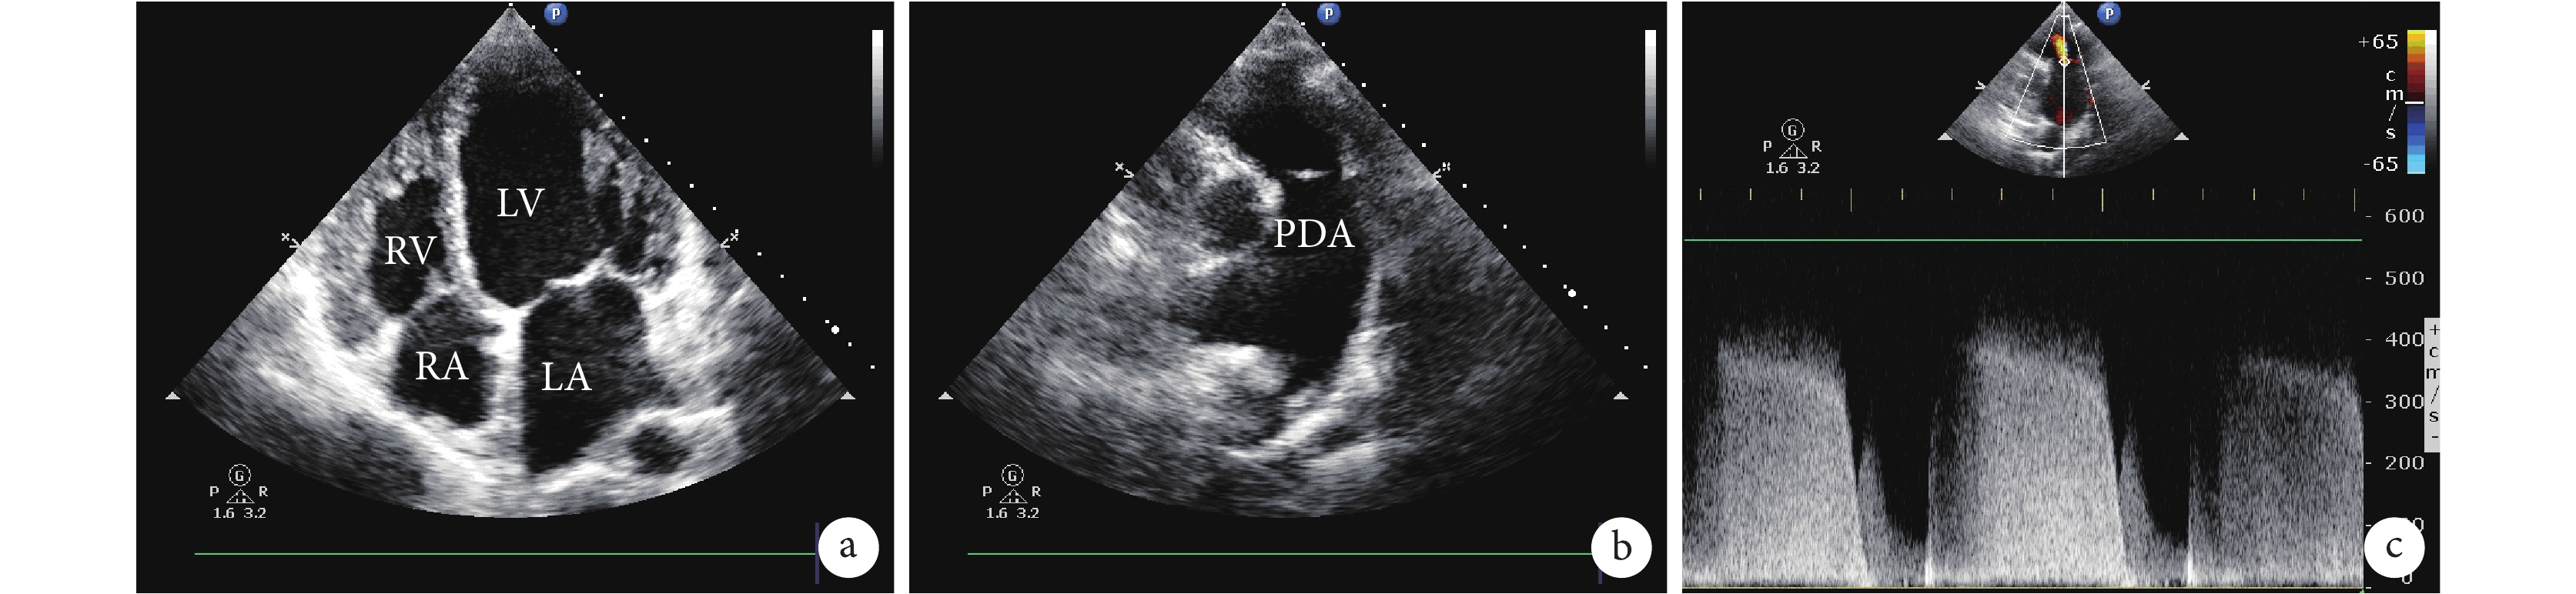

a. 四腔心切面示左心室(直徑 62 mm)、左心房(直徑 44 mm)、右心房(直徑 49 mm)存在明顯擴張;b. 超聲發現動脈導管未閉;c. 肺動脈反流頻譜測量肺動脈收縮壓為 91 mm Hg。LA:左心房;RA:右心房;LV:左心室;RV:右心室;PDA:動脈導管未閉

入院時體格檢查:心率 67 次/min,體溫 36.7℃,呼吸頻率 21 次/min,血壓 100/68 mm Hg(1 mm Hg=0.133 kPa);心臟叩診提示心界擴大,胸骨左上緣有明顯的機械樣連續性雜音,四肢出現差異性紫紺;余未見確切異常。入院即刻心電圖顯示 V1 導聯上 R 波振幅明顯增加,全導聯出現 ST 段壓低(V1-V3 導聯最明顯),心電圖同時提示右心室肥厚。入院后完善心臟彩色多普勒超聲、胸部 CT。床旁超聲心動圖可見心房和左心室均出現不同程度的擴張(圖 1a),同時發現擴張的肺動脈(內徑為 4.4 cm)以及動脈導管未閉(內徑約 20 mm,圖 1b),以及中度三尖瓣反流、二尖瓣反流、肺動脈瓣反流和重度肺動脈高壓(肺動脈收縮壓為 91 mm Hg,圖 1c)。心血管 CT 造影顯示左肺動脈顯著擴張和伴有假腔形成的肺動脈夾層,肺動脈夾層在撕裂遠端形成一處折返(圖 2)。初步診斷考慮:① 先天性心臟病、動脈導管未閉、肺動脈高壓;② 左肺動脈夾層。治療上予以檢測血壓、心率,復查血氣分析,完善先天性心臟病血管 CT 檢查。該例患者重點應明確肺動脈夾層病因,以解除病因為治療目標。